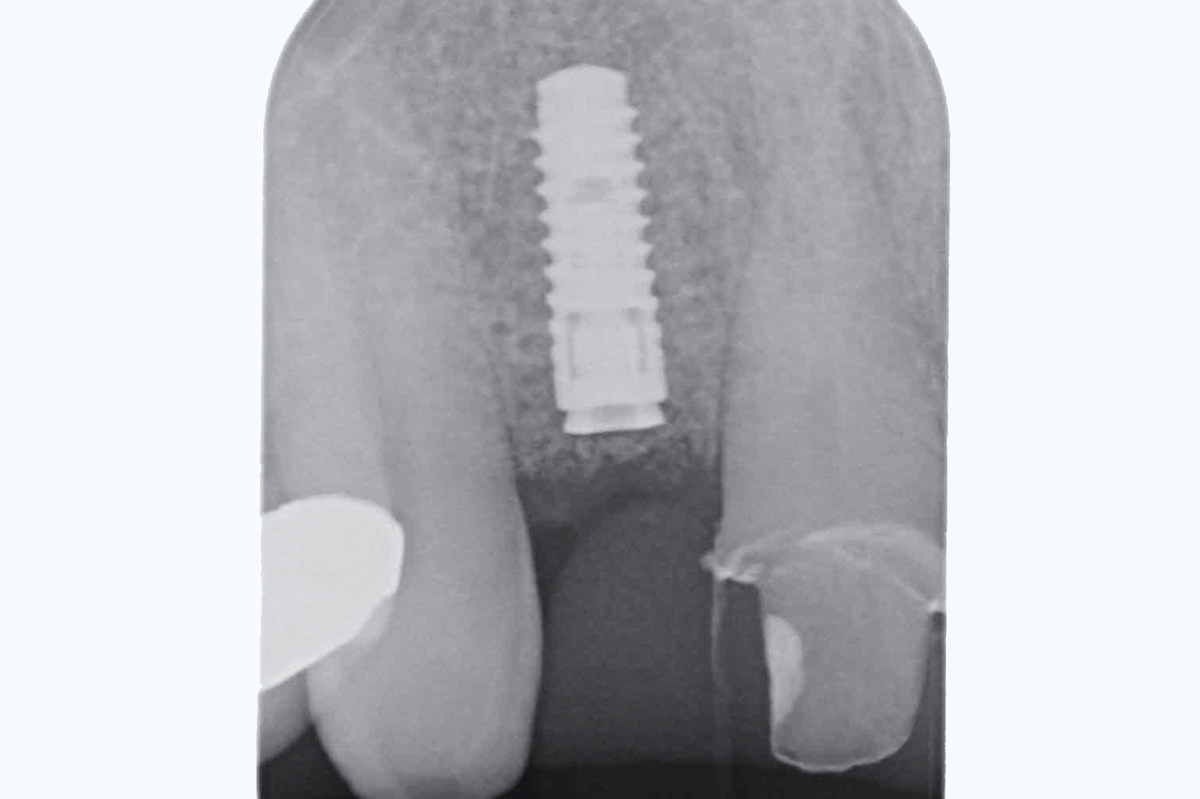

11/19 - Post-op x-ray shows good seating of implantBone augementation with maxresorb® - Dr. R. Cutts